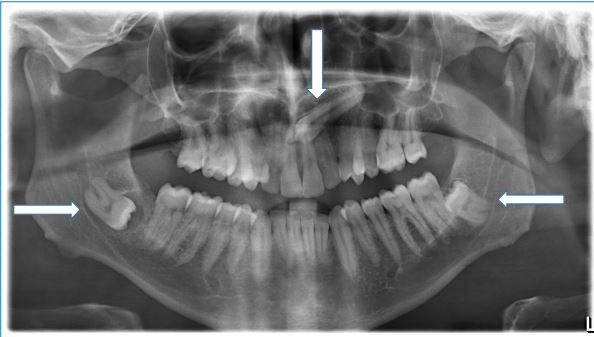

Gömük dişlerin servikal distoni etiyolojisinde yerini göstermek. Servikal distoni tedavisinde nöralterapi uygulamalarının etkinliğini belirlemek. Servikal distoni, boyun ve omuz kaslarını etkiler. Tekrarlayıcı özellikte, tonik ve klonik hareketlerle karektirizedir. Başın anormal postürüne neden olur. Klinik pratikte en sık rastlanılan fokal distoni çeşididir. Hastalığın altında yatan patolojik mekanizma ve etiyoloji tam olarak bilinmemektedir. Gömük dişler sempatik uyaranlara dönüşerek "Bozucu Alan" yaratabilir. Sempatik aşırı stimülasyon, nöral terapi yaklaşımı ile çözülebilir. Olgunun şikayetleri 18 ay önce boyunda istemsiz titreme ve tonik-klonik kasılmalarla başlamıştı. Başka merkezlerde servikal distoni teşhisi konmuştu. Olguya on iki seans nöralterapi tedavisi uygulandı. Olguda, takip sürecinde distoni gelişmedi. Gaz ve şişkinlik sorunları kalmadı. Postur düzelmesine yönelik egzersiz ve nöralterapi injeksiyonları devam etmektedir.